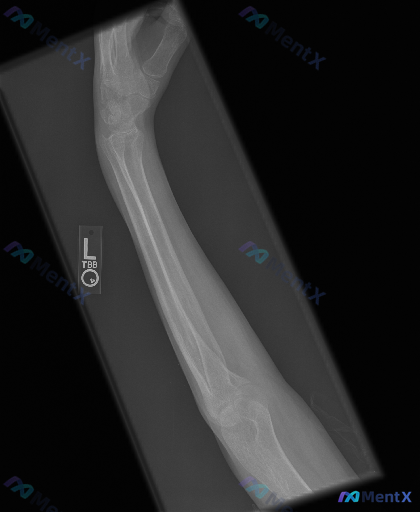

- 影像类型:左前臂斜位X光(标记有“L”)

- 影像所见:

- 投照范围包含肘关节远端和完整腕关节,尺桡骨骨干轮廓清晰,部分重叠;

- 桡骨、尺骨骨干皮质连续,未见明显骨折线、台阶感或透亮裂纹;

- 桡骨头、尺骨近端、桡骨远端及尺骨茎突结构完整,关节对合关系尚可,关节间隙宽度大致均匀;

- 整体骨密度未见显著普遍性稀疏或局灶性异常高密度,未见骨膜反应、溶骨性破坏区或明显软组织占位;

- 周围软组织边界初步观察未见明显异常高密度异物阴影。